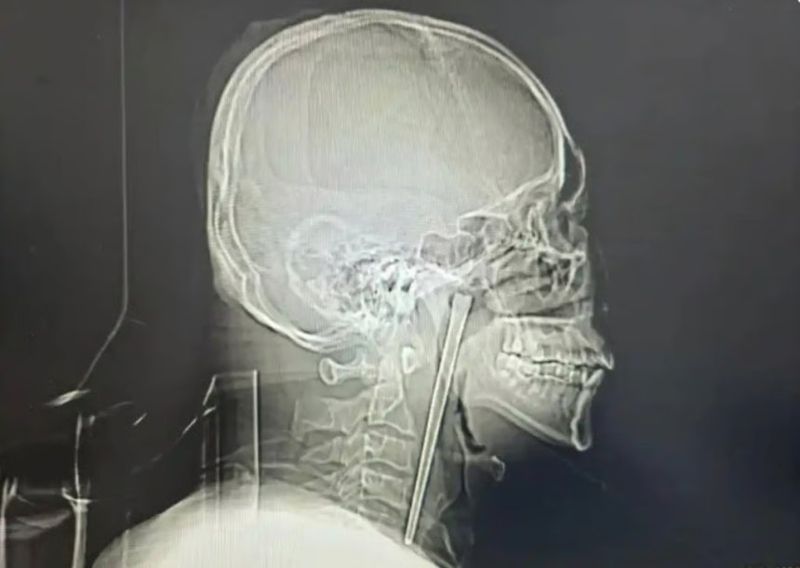

20일 사우스차이나모닝포스트(SCMP)에 따르면 이달 초 중국에 사는 한 남성이 목에 12cm 길이의 금속 젓가락이 박힌 채 8년을 지내다가 최근 수술을 통해 제거했다고 전했다.

정밀 검사 결과 남성이 삼킨 금속 젓가락은 입천장의 뒤에 위치한 목 안쪽 연구개 부위에 박혀 있었던 것으로 확인됐다.

의료진은 "다행히 주변 점막이 손상되지 않았고 성대 기능 역시 정상적으로 유지되고 있었다"고 설명했다.

그러나 남성이 여전히 목 절개 수술을 거부해, 의료진은 절개를 최소화한 최소침습수술을 시도했다. 결국 의료진은 구강을 통해 소량의 출혈만으로 젓가락을 제거하는 데 성공했다. 빠르게 회복한 남성은 며칠 후 퇴원했다.